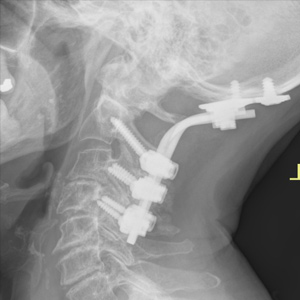

Spinal stenosis (Lumbar) Spinal stenosis (Cervical) Spinal stenosis (Thoracic) Lumbar Disc Herniation Spondylolisthesis Cervical Foraminal Stenosis Vertebroplasty Lumbar Fusion Anterior Cervical Fusion (ACDF) Posterior Cervical Fusion Thoracic Fusion Revision Lumbar Fusion Surgery Facet Joint Cyst Spinal Tumour Minimally Invasive Lumbar Fusion (XLIF) Minimally Invasive Lumbar Fusion (ALIF) Lumbar Fusion (TLIF) Thoraco-lumbar Fusion Lumbar Corpectomy Complex Lumbar Spine Surgery (Spino-pelvic fixation) Complex Cervical Spine Surgery Complex Thoracic Spine Surgery Occipito-cervical Fusion Minimally invasive surgery for thoracic disc herniation Other Related Topics